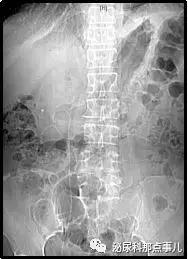

术前KUB

术后KUB